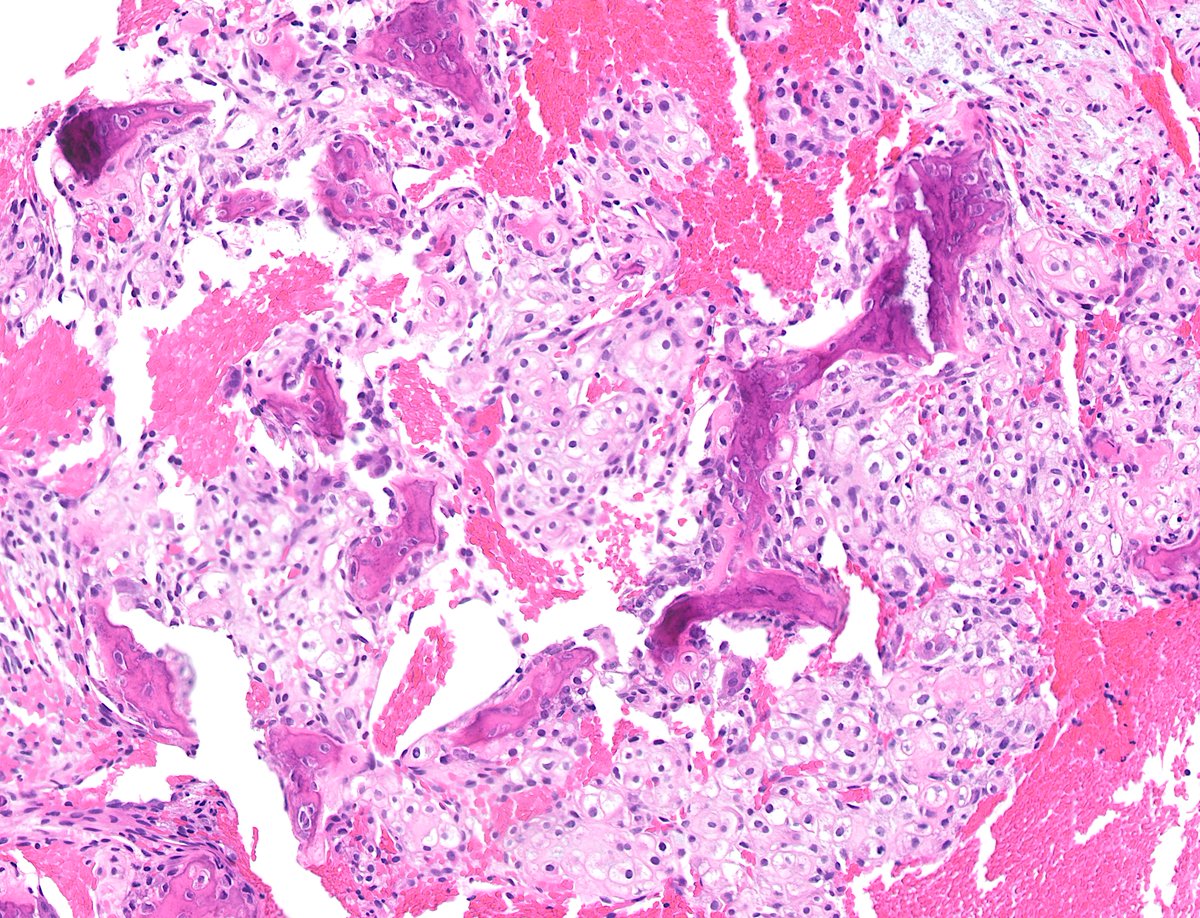

Radiolucency in frontal bone sagittal + axial CT. Here’s a clue: Keep a low power impression Mild expansive remodeling, cortical thinning, radial (spoke) trabecular bone radiating around a central lucency Diagnosis? John Reith Shivani Ahlawat Laura Fayad Lisa Rooper

Check out the latest and greatest from Sintawat Wangsiricharoen, Michael Michal, MD, PhD, Greg Charville, John Gross, MD, published in #VirchowsArchive: tinyurl.com/yc48rhpy Non-cutaneous syncytial myoepitheliomas are identical to cutaneous counterparts. Awesome! #BSTpath #dermpath #PathTwitter